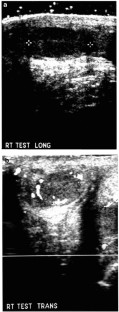

Herman, T., Siegel, M. Meconium Periorchitis. J Perinatol 24, 53–55 (2004). https://doi.org/10.1038/sj.jp.7211014